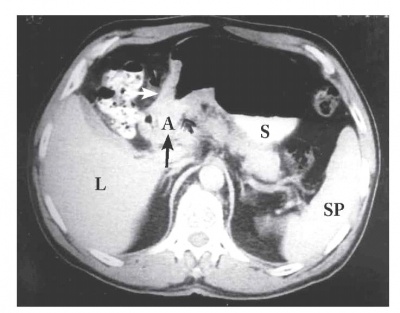

טומוגרפיה ממוחשבת - מאפשרת להדגים את גודל השאת, התפשטותה לאיברים סמוכים, בלוטות לימפה מוגדלות או גרורות לאיברים אחרים (תצלומים 21.3-18.3). ב-CT הדיוק באבחנת T4 הוא 90% וב-T1 הוא 23%.